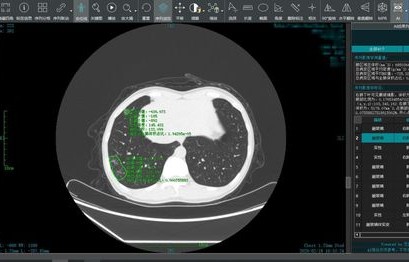

我们需要明确医院CT图像的重要性,CT(Computed Tomography)即计算机断层扫描,是一种常见的医学影像检查手段,通过CT扫描,医生可以获得患者体内器官、组织的高清三维图像,为疾病的诊断和治疗提供重要依据,CT图像在医疗领域具有极高的价值。

随着移动互联网的普及,许多人希望能够在手机上查看医院的CT图像,从技术角度来看,手机端查看CT图像存在诸多局限性,手机的屏幕尺寸和分辨率有限,无法满足高清、大尺寸的医学影像显示需求,手机端缺乏专业的医学影像处理软件和设备,无法对CT图像进行准确的解读和分析,手机端的安全性、隐私性和稳定性也无法满足医学影像的特殊需求。